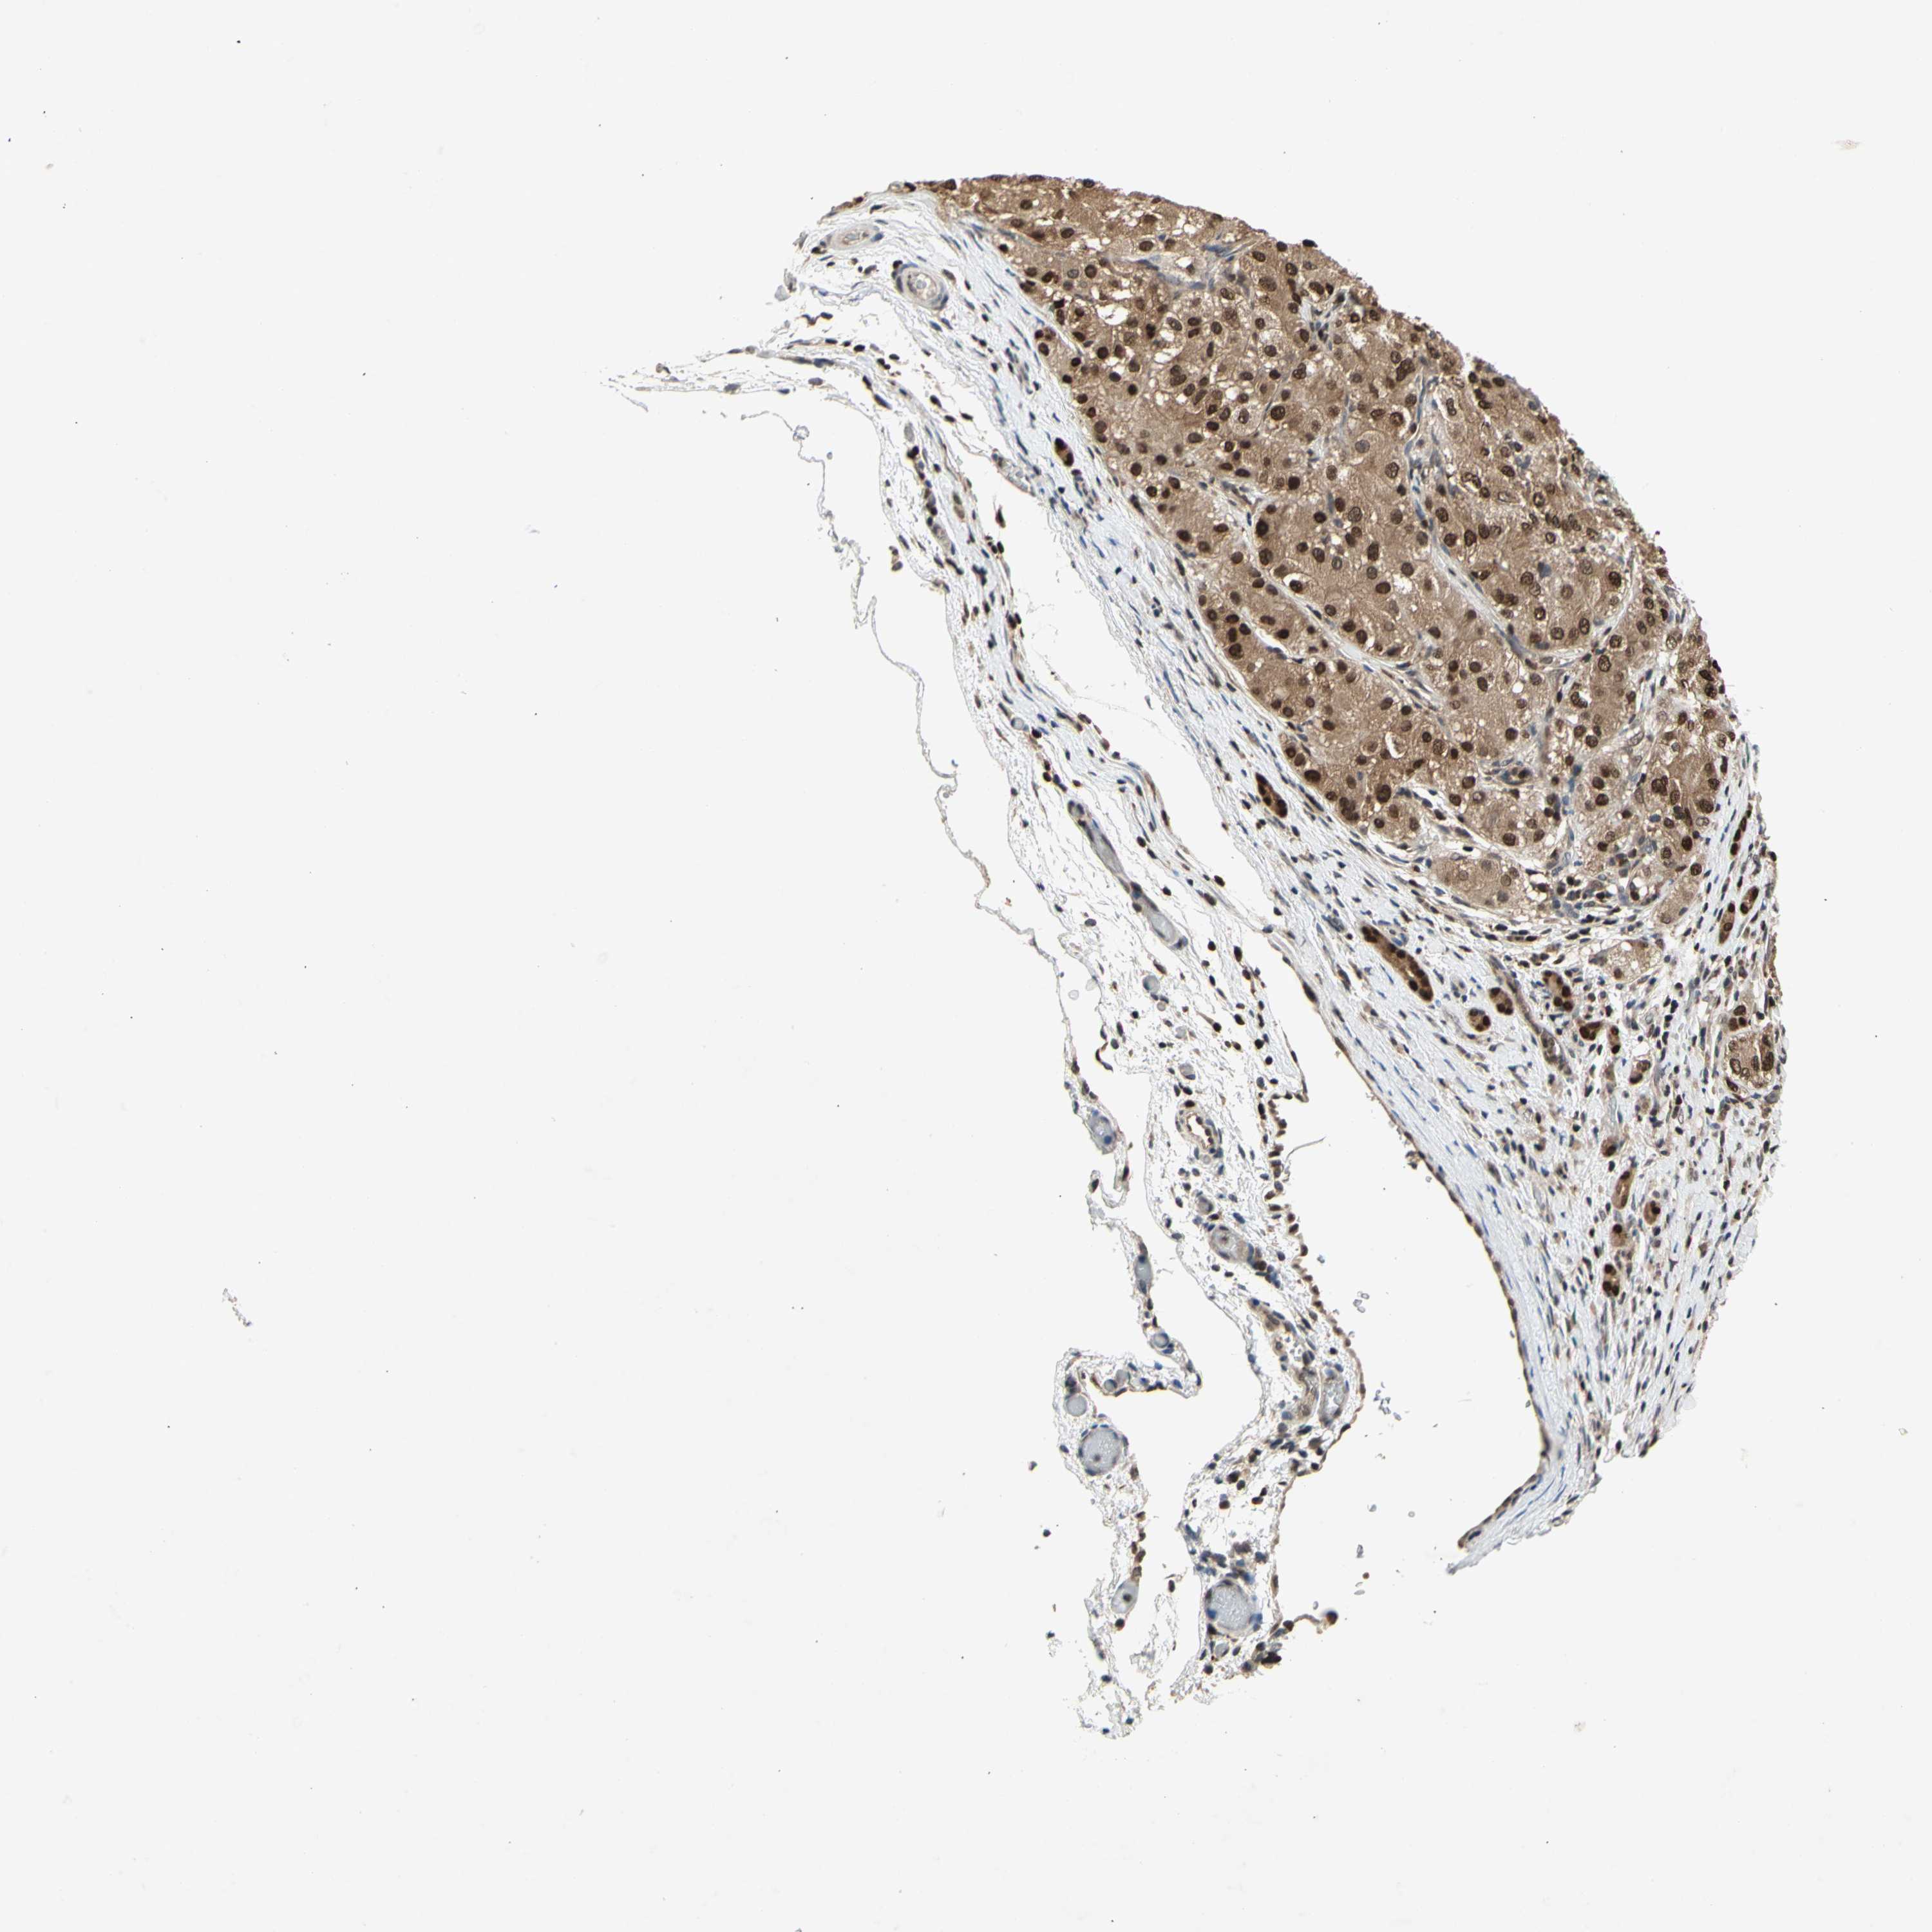

LIVER CANCER - Protein expressioni

A mouse-over function shows sample information and annotation data. Click on an image to view it in a full screen mode. Samples can be filtered based on level of antibody staining by selecting one or several of the following categories: high, medium, low and not detected. The assay and annotation is described here.

Note that samples used for immunohistochemistry by the Human Protein Atlas do not correspond to samples in the TCGA dataset.

Antibody stainingi

Antibody staining in the annotated cell types in the current human tissue is reported as not detected, low, medium, or high, based on conventional immunohistochemistry profiling in selected tissues. This score is based on the combination of the staining intensity and fraction of stained cells.

Each image is clickable and will lead to virtual microscopy that enables deeper exploration of all samples and also displays staining intensity scores, fraction scores and subcellular localization as well as patient and tissue information for each sample.

Antibody HPA001538

Antibody CAB008632

Staining

High

Medium

Low

Not detected

Intensity

Strong

Moderate

Weak

Negative

Quantity

>75%

75%-25%

<25%

None

Location

Nuclear

Cytoplasmic/membranous

Cytoplasmic/membranous,nuclear

Cholangiocarcinoma

Carcinoma, Hepatocellular, NOS